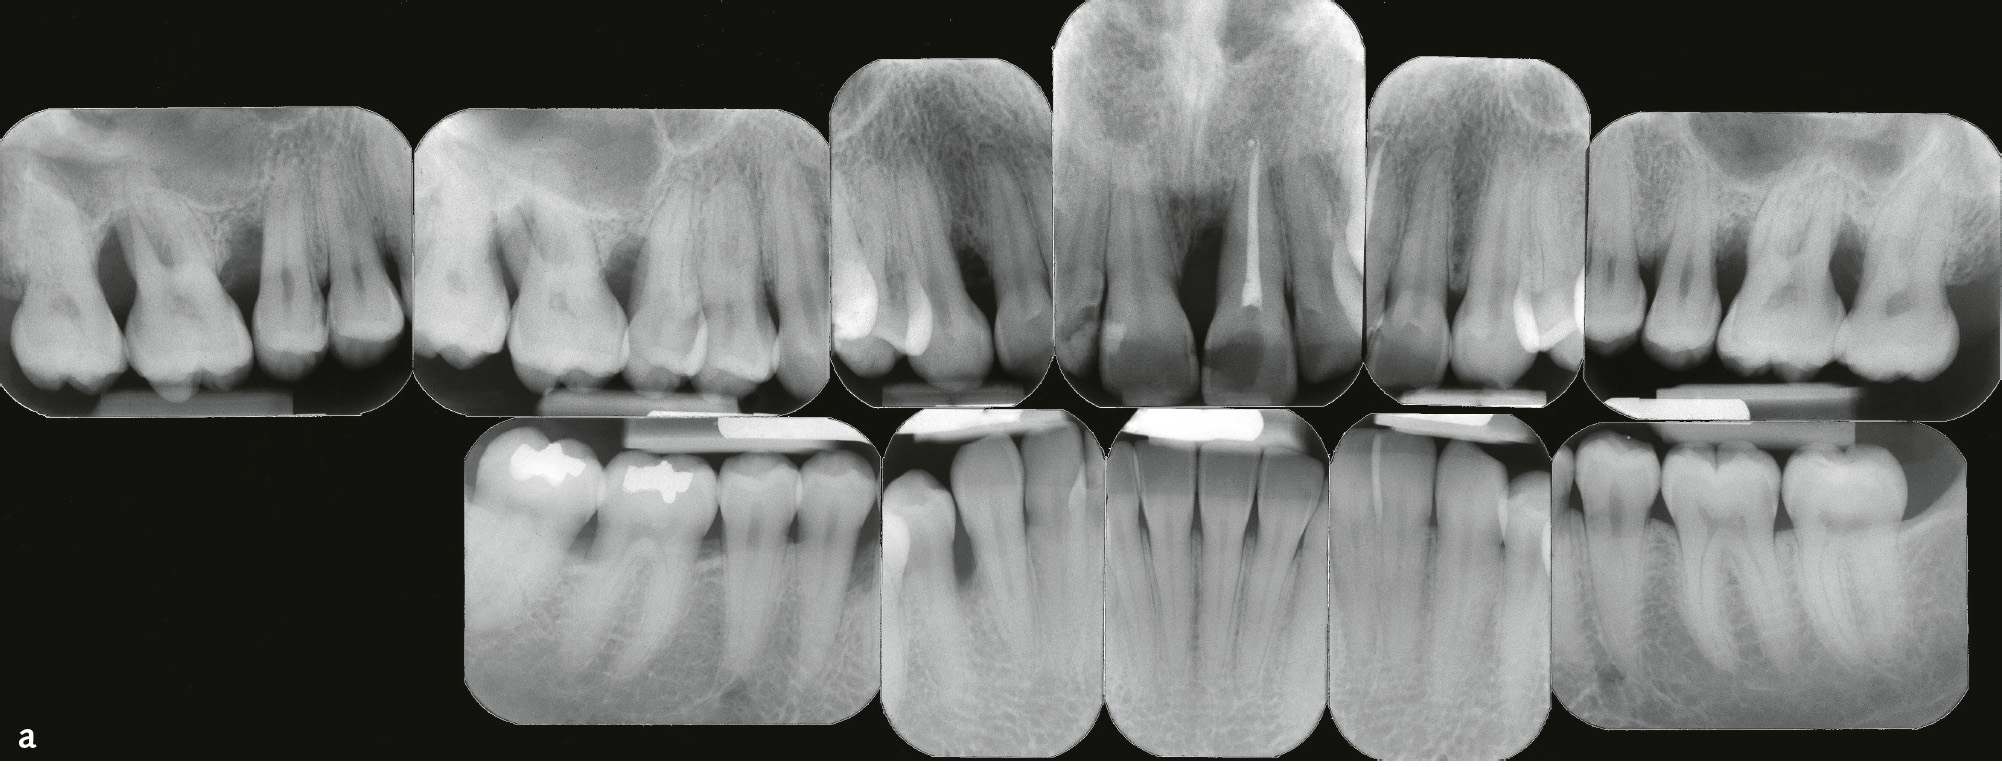

Die Parodontitis wird nach Schweregrad und Komplexität in vier Stadien unterteilt (Stadium I bis IV; Tab. 7). Primär sollte dafür klinischer Attachmentverlust (CAL) zugrunde gelegt werden, falls dazu keine Angaben vorliegen, röntgenologischer Knochenabbau (Abb. 4a). Dabei kann das Ausmaß als lokalisiert (< 30 % der betroffenen Zähne), generalisiert (≥ 30 % der betroffenen Zähne) oder Molaren-Inzisiven-Muster (s. „lokalisierte aggressive Parodontitis“) beschrieben werden. Im Unterschied zur Klassifikation von 19997 wird nur approximaler klinischer Attachmentverlust berücksichtigt. CAL aufgrund von Rezessionen, die keine entzündliche Pathogenese haben müssen8, bleiben unberücksichtigt. Für die Berechnung des Ausmaßes wird die Zahl der Zähne und nicht die der Stellen zugrunde gelegt (Tab. 7). Nicht nur CAL und Knochenabbau determinieren den Schweregrad, sondern auch durch Parodontitis eingetretener Zahnverlust. Es ist nicht mehr möglich, eine Parodontitis durch Extraktionen in einen niedrigeren Schweregrad zu transferieren. Sondierungstiefen (ST) spielen wieder eine Rolle und markieren zusammen mit BOP (Bluten auf Sondieren) den Unterschied zwischen einem stabilen Zustand nach erfolgreicher Parodontitistherapie (s. Tab. 3 und 4) und Parodontitis (Tab. 7). Entsprechend der Geschwindigkeit der Gewebezerstörung werden drei Progressionsgrade unterschieden: Grad A: langsame Progression, Grad B: moderate Progression, Grad C: rasche Progression (Tab. 8)9,10.

Abb. 4a bis c Patientin im Alter von 24 Jahren mit generalisierter aggressiver Parodontitis18, Parodontitisstadium III (Molaren-Inzisiven-Muster) Grad C. a) Röntgenstatus: Knochenabbau bis ins apikale Wurzeldrittel an den Zähnen 16, 21 und 26 (Stadium III), im Unterkiefer geringerer Knochenabbau bis 50 % der Wurzellänge an Zahn 44, kein Zahnverlust, aber Sondierungstiefen ≥ 6 mm an Zahn 16, Grad-III-Furkationsbeteiligung an Zahn 16 und 26, distal Zahn 16 Knochenabbau 70 % der Wurzellänge (geteilt durch das Lebensalter = 2,9; Grad C). b und c) Klinische Ansicht: keine supragingivale Plaque, Destruktion überschreitet Erwartungen durch Biofilmauflagerungen (Grad C).